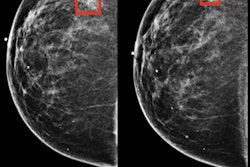

In breast imaging, there are a lot of opportunities for AI in checking image quality, analyzing breast density, and creating 2D mammography images from 3D digital breast tomosynthesis exams to avoid having to acquire both exams separately, according to Safdar.

There's also ongoing work with applying AI to diagnostic mammography, ultrasound, or other modalities in women's imaging, including AI-based computer-aided detection (CAD). Comparisons between AI and radiologist performance are a little spurious at this time, however, Safdar said.